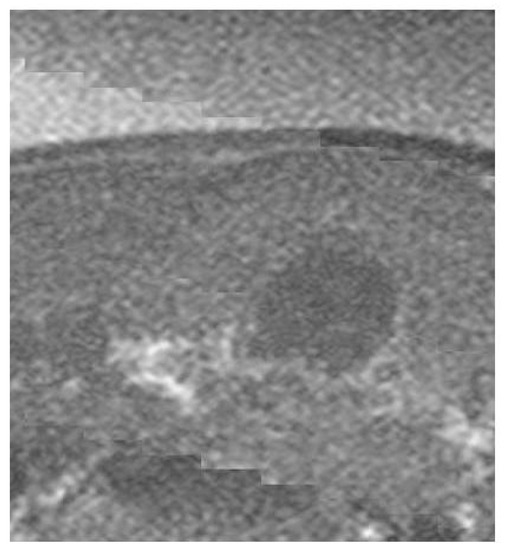

2.4. Experimental Imaging of an Abdominal Phantom using the Proposed Method of Compensating for the Sound Velocity Distribution to Correct Beamforming

3.2. Imaging of an Abdominal Phantom